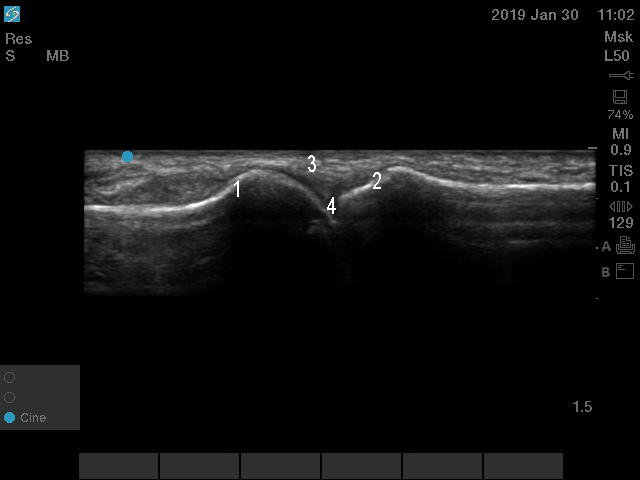

Foot & Ankle MTP Joint Anatomy Long Axis Image

1. Metatarsal Head

2. Proximal Phalanx

3. Extensor Tendon

4. MTP Joint